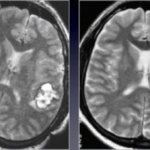

Inhibited reactions, impaired concentration, weakened memory force you to go to a neurologist for a prescription.

Brain training This may be interesting: What you need to know about memory: 9